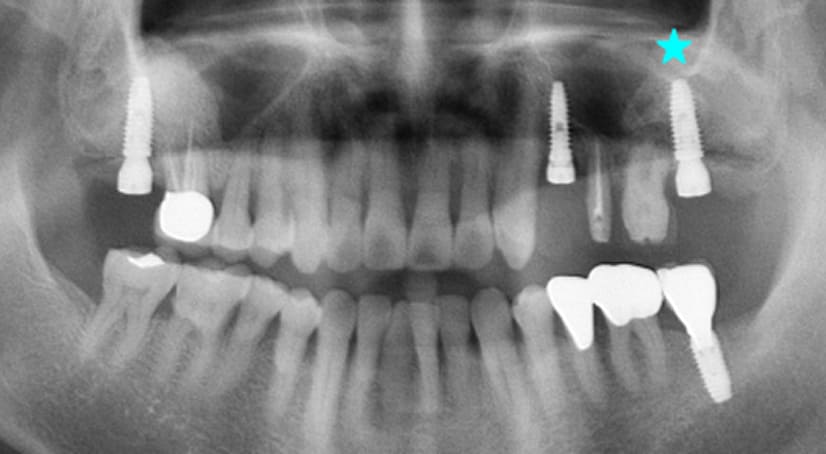

13+ 年

-

种植体植入:2012 年 9 月 -

最终修复体:2013 年 1 月 -

随访:13 年(2025 年 1 月)